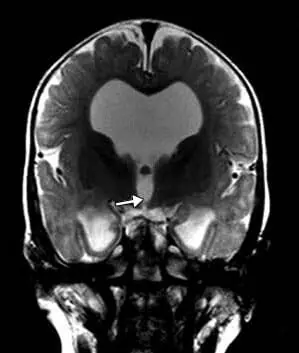

頭部磁気共鳴映像法では、テント上水頭症、視交叉陥凹のバルーニング、薄い脳梁、側脳室および第3脳室の拡張、透明中隔の欠如、および脳の低髄鞘化が明らかになった(図2)。

図2. 磁気共鳴画像法T2強調矢状画像。 脳梁は薄かった。 磁気共鳴画像法T2強調冠状断像。